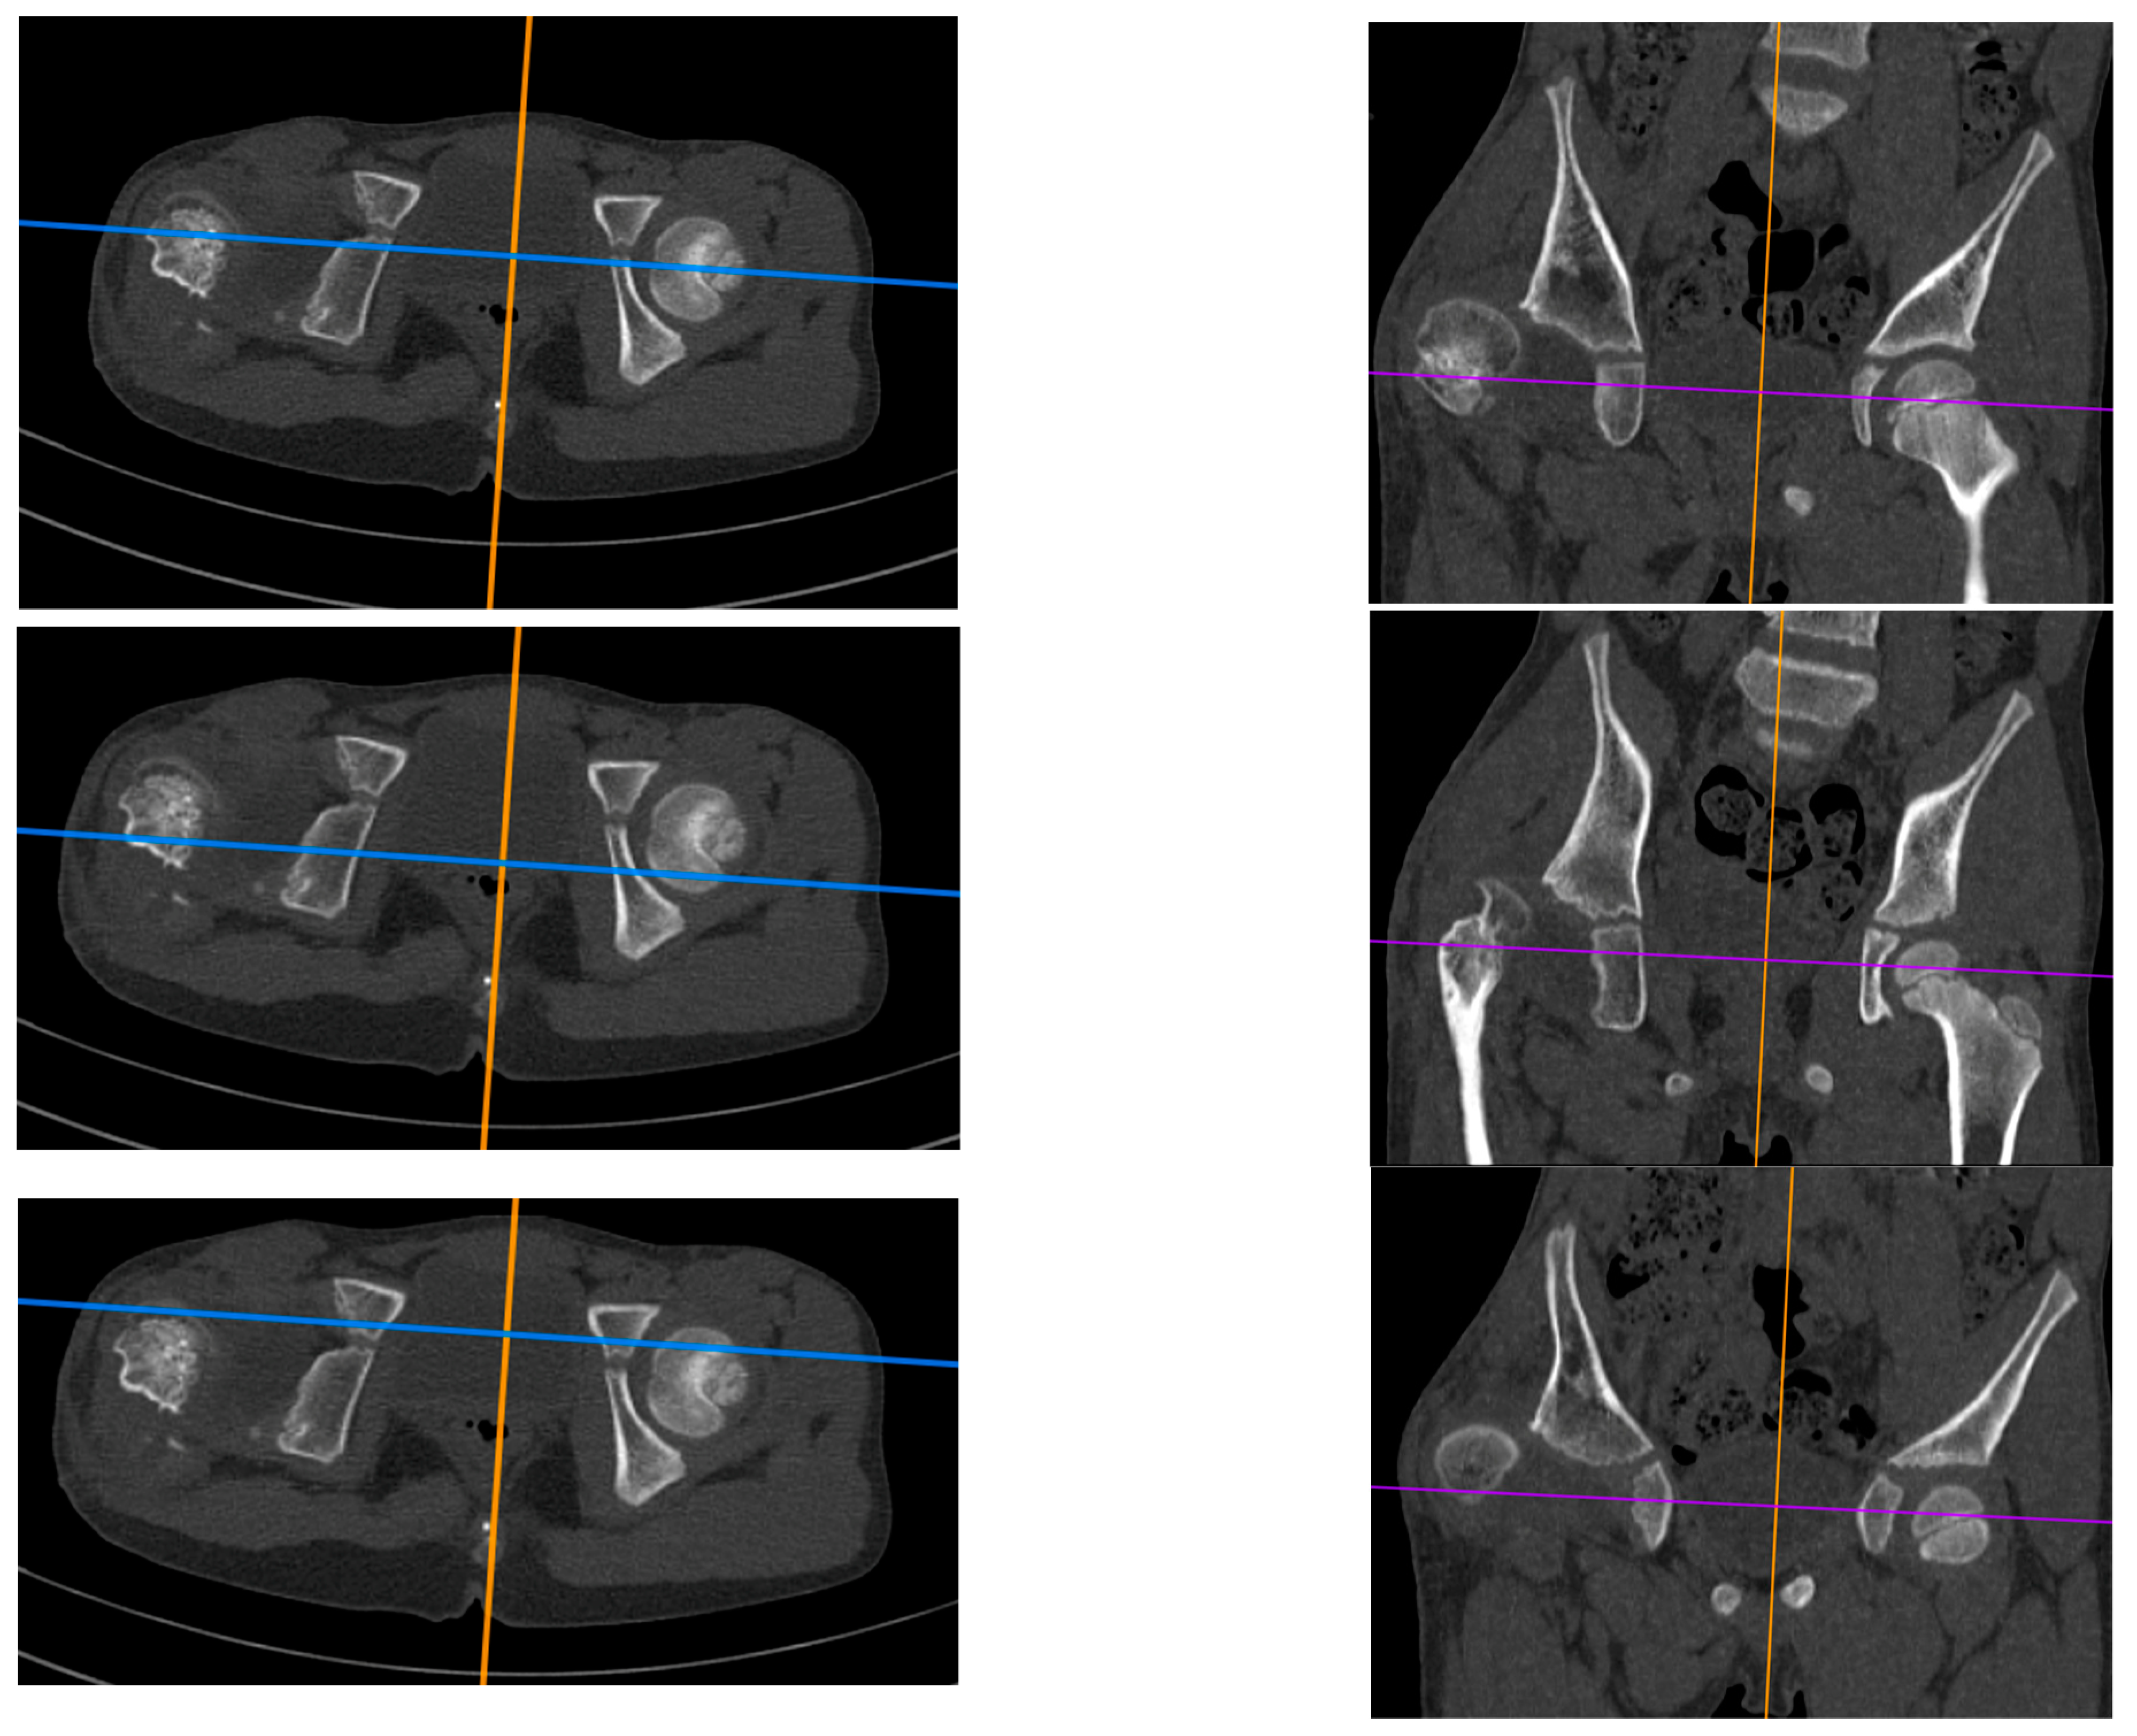

The study is a retrospective cohort review. We have reviewed medical histories and radiograms. The patients were examined three times: (1) before hip reconstruction surgery, (2) before femoral lengthening, and (3) at follow-up. The patients underwent standard AP hip joints radiograms, internal rotation hip radiograms, Rippstein position radiograms [21], and standing lower limbs AP long cassette radiograms. We have measured the Center-Edge Angle (CEA, Wiberg), the Acetabular Inclination (AI), the Neck-Shaft Angle (NSA), and the Antetorsion Angle (AT), and the Shenton line was also evaluated [22,23,24,25,26,27]. Femoral torsion normal values were adapted from the Tönnis study [23], femoral retrotorsion was accepted as a negative true AT value, and diminished AT was accepted as <20 deg. Computed Tomography (CT) scans were available in all 6 patients with hip instability. The following parameters were measured on CT scans [18,28,29,30]: Acetabular Anteversion (AA), Axial Acetabular Index (AAI), and Acetabular Inclination in the anterior (AIa), middle (AIm), and posterior (AIp) part of the acetabulum. CT scans with plane presentation and measurements are shown in Figure 2 and Figure 3. Statistical analysis was performed with the use of STATISTICA v13.3 and PQStat v1.8.4. Significance was determined as p < 0.05.

Figure 2.

CT examination of patient with right hip dislocation. Left: transverse view, right: coronal view. Evaluation of medial (first row), posterior (middle row), and anterior (last row) parts of the acetabulum.

All five included patients presented a deficit of the coverage of the posterior part of the acetabulum. These patients presented a normal Acetabular Inclination angle on standard hip radiograms and a pathological high Acetabular Inclination angle measured in the posterior part of the acetabulum on CT scan (>25 deg); the difference between CT and RTG for the AI measured in the posterior part was statistically significant (28.3 deg vs. 19.8 deg, p < 0.01). Another finding was that the AI measured in the anterior, middle, and posterior parts of the acetabulum were significantly different in the CFD hip joint (16.2 deg vs. 22.4 deg vs. 28.3 deg, p < 0.01), with no such difference at the healthy side. The difference in AI measured in the posterior vs. anterior part of the acetabulum was 11.1 deg in the CFD unstable hip joint, and it was significantly higher than on the healthy side (11.1 deg vs. 3.0 deg, p < 0.05). CT analysis is shown in Table 8. A CT scan of a patient with hip instability is shown in Figure 2 and Figure 3.